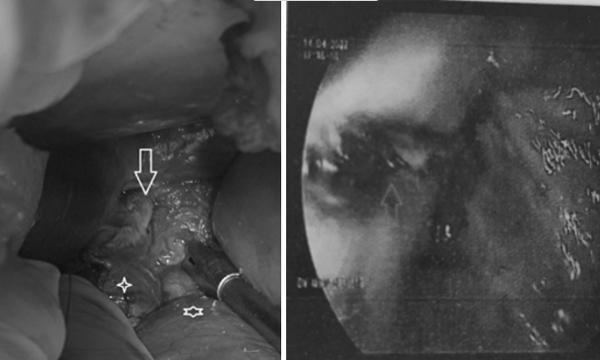

Sau bữa nhậu buổi trưa, người đàn ông 46 tuổi nôn nhiều lần, đau lan khắp bụng ra sau lưng, đến mức khó thở.